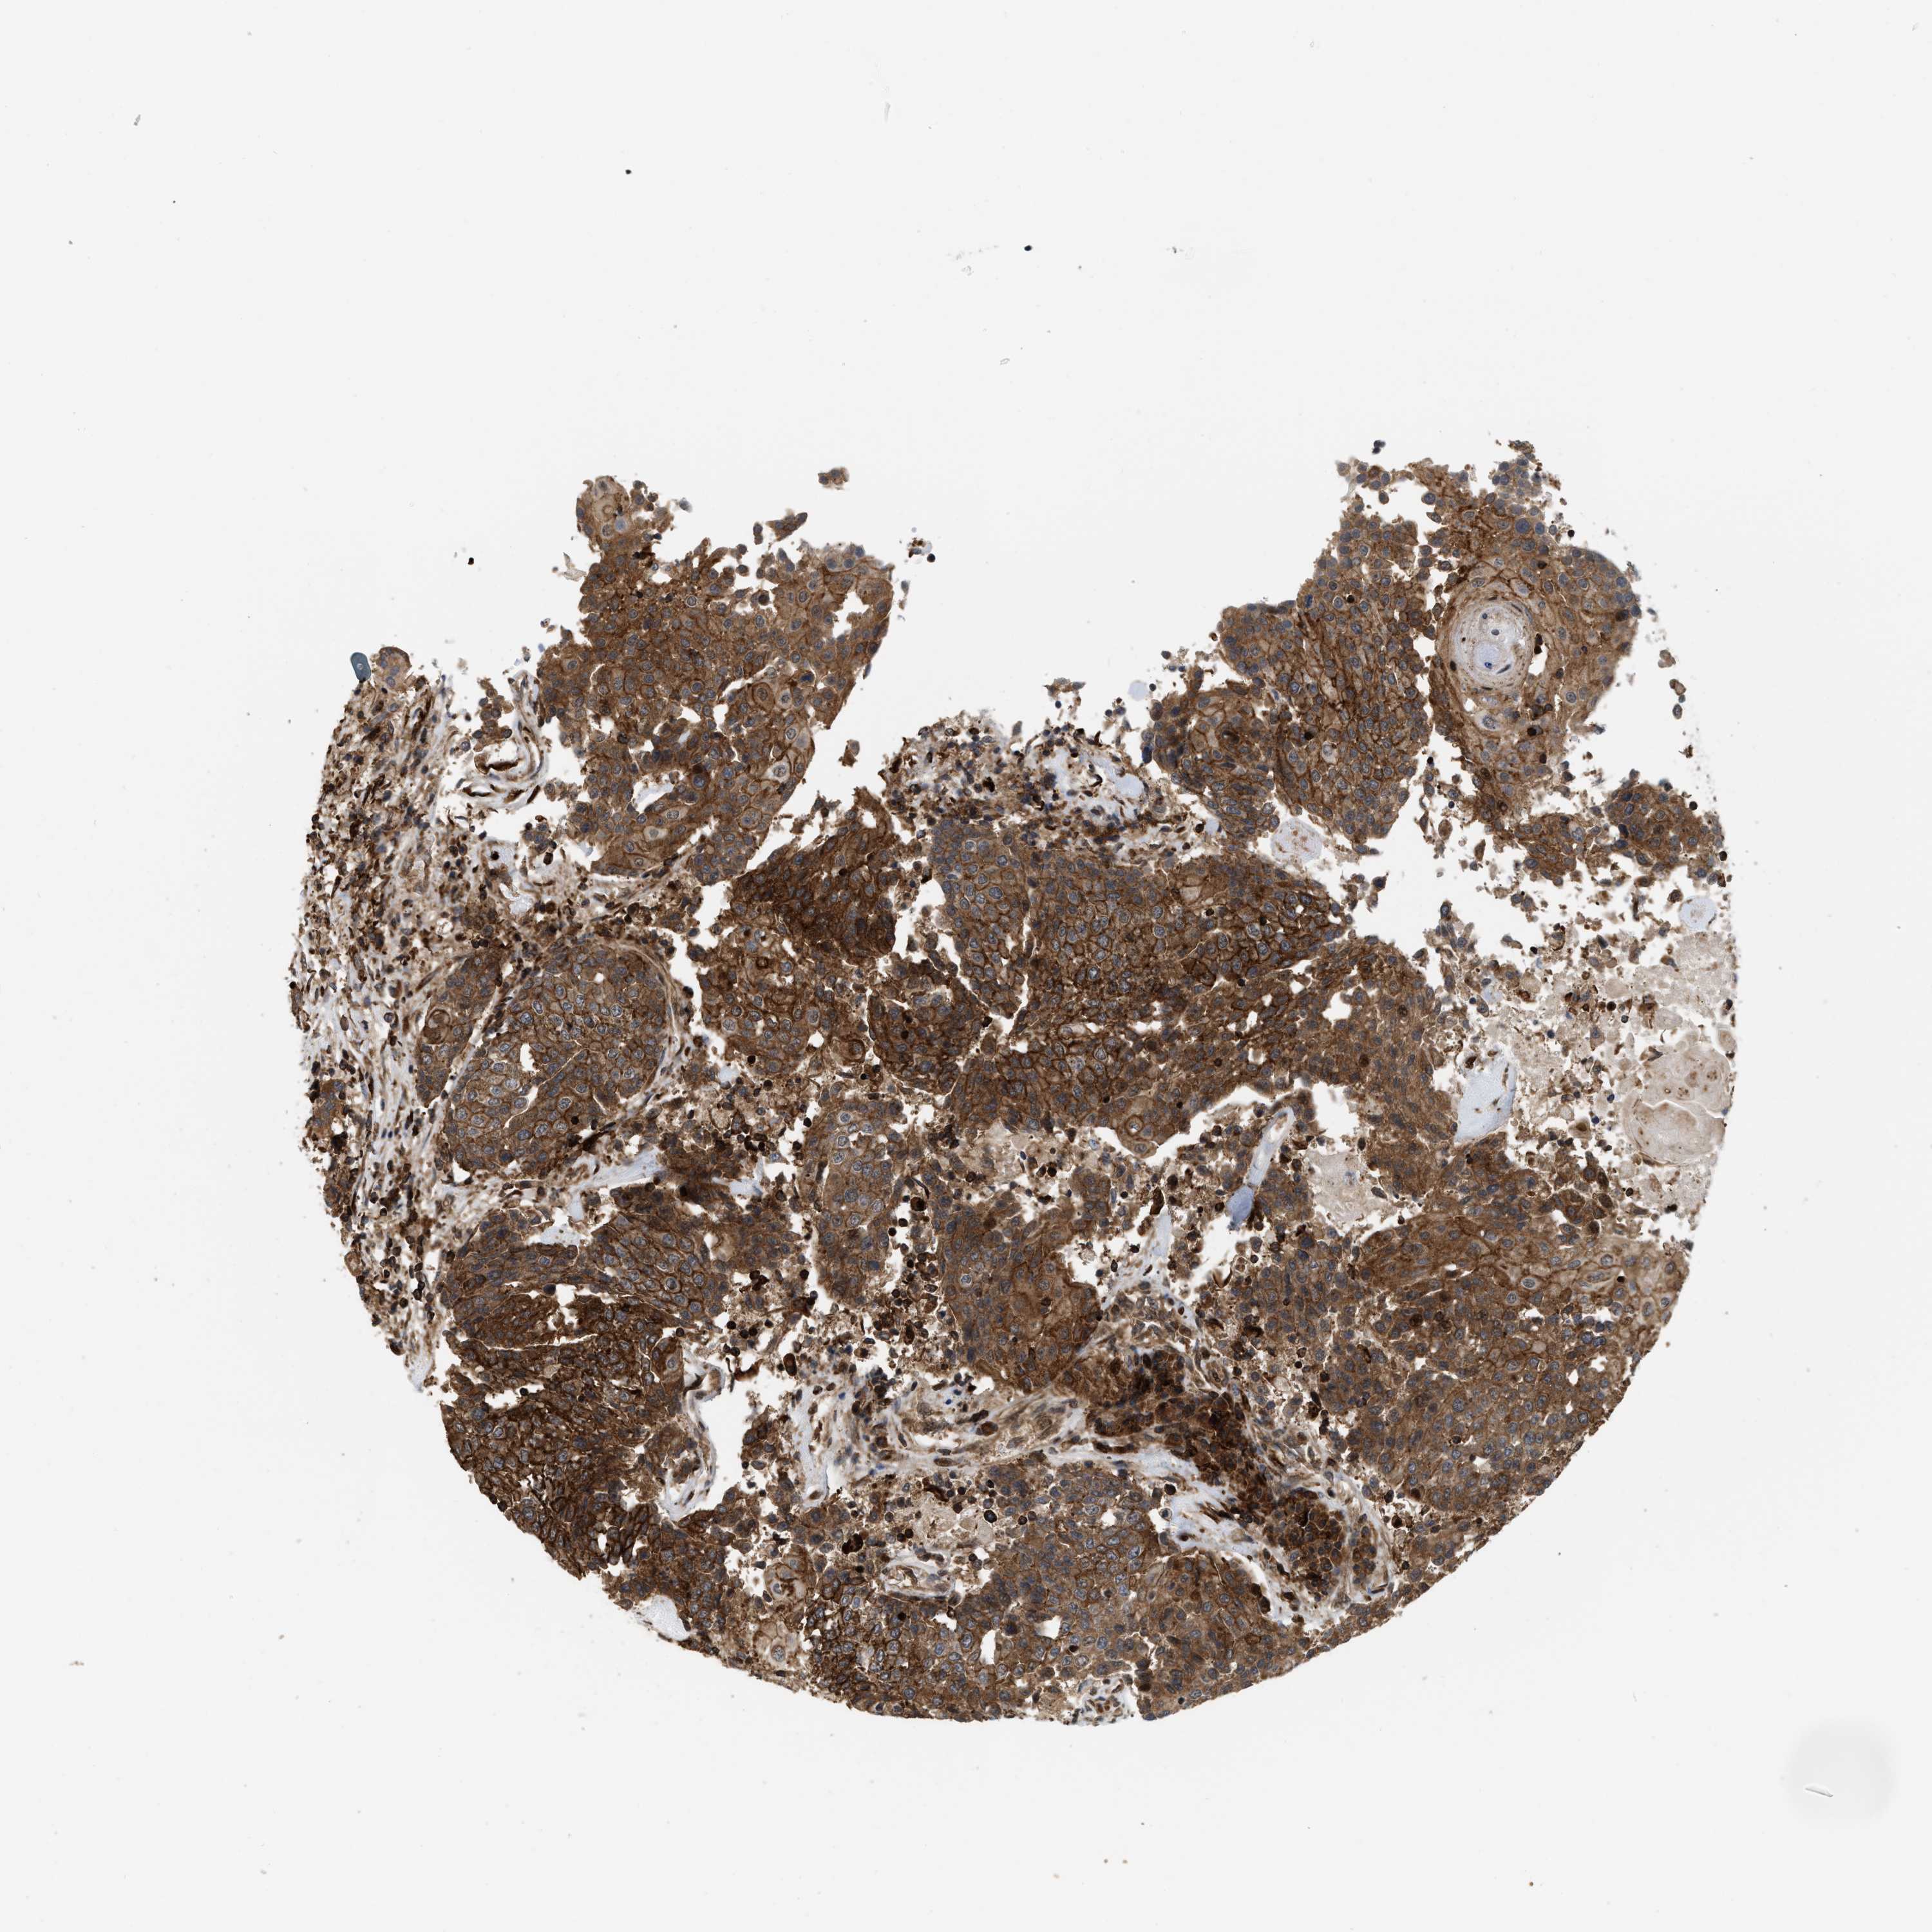

UROTHELIAL CANCER - Protein expressioni

A mouse-over function shows sample information and annotation data. Click on an image to view it in a full screen mode. Samples can be filtered based on level of antibody staining by selecting one or several of the following categories: high, medium, low and not detected. The assay and annotation is described here.

Note that samples used for immunohistochemistry by the Human Protein Atlas do not correspond to samples in the TCGA dataset.

Antibody stainingi

Antibody staining in the annotated cell types in the current human tissue is reported as not detected, low, medium, or high, based on conventional immunohistochemistry profiling in selected tissues. This score is based on the combination of the staining intensity and fraction of stained cells.

Each image is clickable and will lead to virtual microscopy that enables deeper exploration of all samples and also displays staining intensity scores, fraction scores and subcellular localization as well as patient and tissue information for each sample.

Antibody HPA019515

Staining

High

Medium

Low

Not detected

Intensity

Strong

Moderate

Weak

Negative

Quantity

>75%

75%-25%

<25%

None

Location

Urothelial carcinoma, Low grade

Urothelial carcinoma, High grade